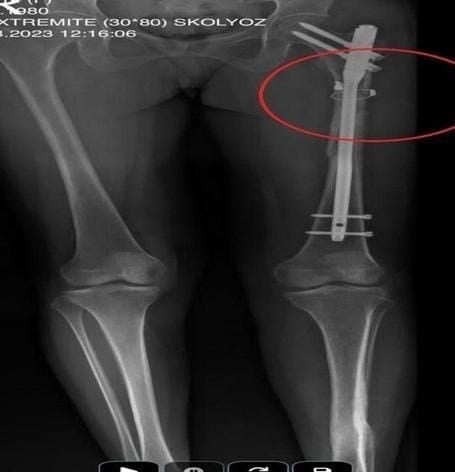

Cinayetin ardından aynı silahla sevgilisini hedef alan Sarıkaya, Fatma O.’yu 8 kurşunla yaraladı. Özaslan’ın cesedini önce çarşafa, ardından kokuyu önlemek için streç filme sararak sakladı. Sarıkaya, yaralı sevgilisinin hastaneye gitmesine izin vermedi; eczaneden aldığı malzemelerle pansuman yaptı. İddianameye göre Sarıkaya, yaralı halde rehin tuttuğu kadına 21 gün boyunca cinsel saldırıda bulundu.